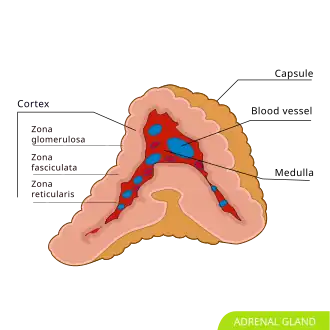

Adrenal gland; the medulla (center, red) is the origin of the pheochromocytoma.

Pheochromocytoma (British English: phaeochromocytoma) is a rare tumor of the adrenal medulla composed of chromaffin cells and is a pharmacologically volatile, potentially lethal catecholamine-containing tumor of chromaffin tissue.[4] It is part of the paraganglioma (PGL).[2][5][6] These neuroendocrine tumors can be sympathetic, where they release catecholamines into the bloodstream which cause the most common symptoms, including hypertension (high blood pressure), tachycardia (fast heart rate), sweating, and headaches.[7][8] Some PGLs may secrete little to no catecholamines, or only secrete paroxysmally (episodically), and other than secretions, PGLs can still become clinically relevant through other secretions or mass effect (most common with head and neck PGL).[9] PGLs of the head and neck are typically parasympathetic and their sympathetic counterparts are predominantly located in the abdomen and pelvis, particularly concentrated at the organ of Zuckerkandl at the bifurcation of the aorta.[10]